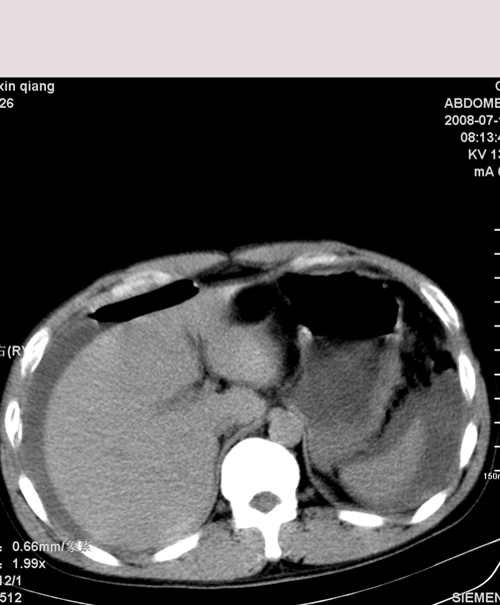

以下是引用muzi888在2008-7-15 10:45:00的发言:[br]大量腹腔积液,气腹,肾皮质弧形高密度影,诊断;1 空腔脏器穿孔 2 右肾包膜下血肿

以下是引用随光逐影在2008-7-15 11:18:00的发言:[br]考虑为:1)腹部空腔脏器穿孔。2)右肾破裂并肾包膜下血肿,肾盂积血。3)腹水(血)。